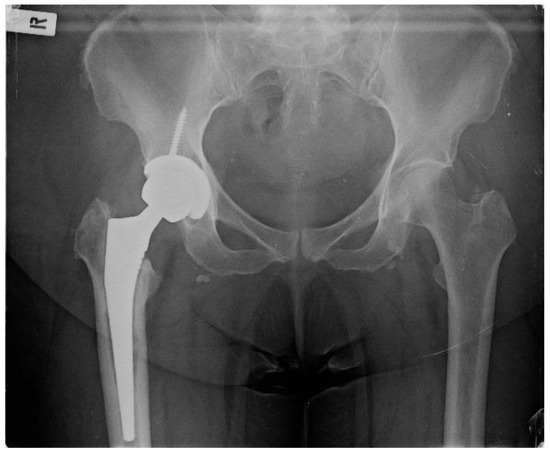

Taking into deliberation the presence of recurrent copious infections in our patient during the first postoperative year, the presence of an atypical pathogen responsible for the PJI and her entire past medical history, it was deduced that the patient might feature an impaired immune system. Consequently, the risk of revision THA surgery was regarded as highly elevated. She was referred to a preeminent immune system specialist physician. Still, no solid inferences could be drawn to explain the multiple infection incidents, albeit without excluding the notion of a weakened immune system. The patient continued to complain about considerable hip pain and an inability to sustain full weight bearing since she had the hip spacer for an extended period and insisted on having a new hip operation. She was thoroughly counselled that, if a revision THA was performed, the peril of a potential new PJI was exceptionally high. Eighteen months from the spacer placement, the patient featured no clinical infections or hospitalizations during the last 5.5 months with negative inflammatory markers and no indications of hip wound infection. After diligent consent, the patient was reoperated on, and a typical revision THA (Avenir Femoral Stem and ZCA All-Poly Acetabular Cup, Zimmer Biomet Holdings Inc., Warsaw, Indiana, United States) was executed utilizing the same posterior approach that was employed in the first operation at our Institution (Figure 4). Intraoperatively, no evident indications of remaining infection were observed regarding the bones and surrounding soft tissues, while bone stock was sufficient. In case that any tissue or fluid with the suspicion of infection was presented in the operating field, no new arthroplasty materials would have been implanted.

Figure 4. Postoperative hip X-ray after revision THA.